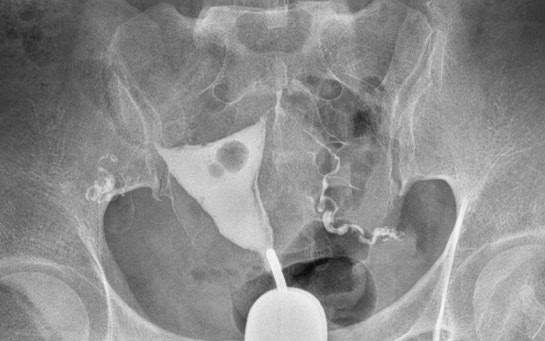

베테기의 사용도 2개월간하고 앱도 쓰고 봤지만 성공하지 않았으므로 시험 관을 하려고 대전 마리아 병원을 지인에게 권유 받게 된 산전 검사는 모두 좋아 마리아가 소개하고 준 선사 영상 의학과에 나팔 선관 조영 촬영을 했어요 주변의 나팔 관 조영술이 아프다고 들었는데, 설마 나는 다를 것이라고 했는데 나팔 관 조영술이나 나팔 관 조영술은 같은 검사!무방비 상태로 하는데, 의사”약이 들면 아픕니다~” 아프면 말하세요~” 하자마자 아픕니다~소리 쳤어요(눈물)!3초 정도 한 것 같은데,많이 아픕니다 의사가 약을 조금밖에 안 들어갔는데 벌써 아픈가요?하지만 나는 자신의 장기가 터질 것 같고 화장실에도 가고 싶은 느낌!순간 현기증이 나고 현기증이 난다고 했는데 긴장하고 그렇게 될지도 모르니까 긴장을 풀어 힘을 빼고 달라며 또 약을 넣긴 하지만 내가 아픕니다!소리를 내서 의사가 너무 아파하는 것인데 이번 검사합니까?하지만 이번에 또 하고 싶지 않다고 생각한다.조금 쉬었다 하면 안 될까요?너무 아픕니다~ 그렇게 여러 차례 조금씩 약을 더 넣어 아프다고 외치고(웃음)결국 촬영을 했습니다!결과를 확인하는 데 다른 분을 보이세요 하지만, 교과서 같은?너무 완벽하게 보입니다만 저는 직접 봐도 보이지 않습니다.하지만 의사가 다른 각도에서 찍은 것을 보이면서 난관이 조금 보이는데, 너무 시달려서 약을 많이 안 넣서 확실히 안 보인다고 생각합니다.모두 막히거나 이상이 있게 보이지 않고 괜찮다고 소견서를 주는데 눈물이 똑~~~눈물 많은 느낌이었습니다. 의사도 나 같은 환자는 처음이었던 것 같군요 끝까지 친절히 대해 주셔서 아프지 않게 배를 쓰다듬어 주고~정말 감사합니다. TT

이렇게 소견서를 받고 왔습니다~ 비용은 4만4천원 정도~ 다른 분들은 아플까봐 미리 타이레놀을 먹고 간다는데 저는 검사하고 나서 알게 된 막힌 분들이 아프다고 하는데 저는 열려 있어도 너무 아팠어요 저는 예민한 성격이고 생일도 몸의 변화라고 생각해요~TT 그래서 더 아픈 것 같아요 그래도 끝났으니 다행이네요~ 다음 고통은 다음에 생각하기로~~~TT